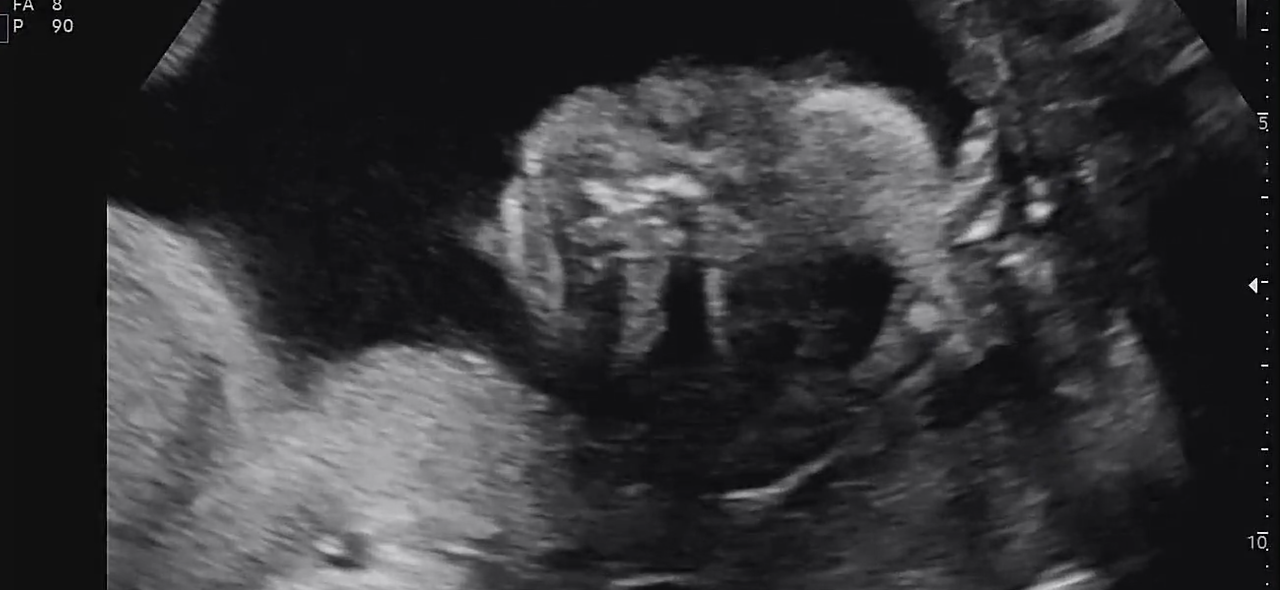

정밀 초음파는 생각보다 오래 걸렸다.

30분 가까이 이어진 검사 동안

손가락, 발가락, 귀, 콧구멍까지

아이는 하나하나 자세히 확인되었다.

22주 정밀초음파

결론은 단순했다.

어떤 부분도 문제없이, 아주 건강하다는 말.